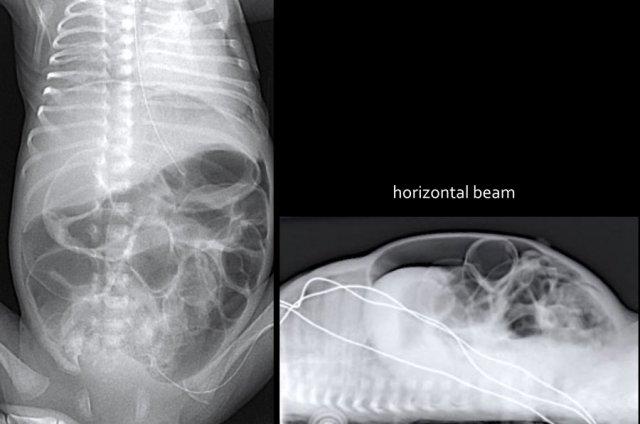

Các dấu hiệu bao gồm:

- Nhiều quai ruột non giãn

- Khí trong thành ruột (Pneumatosis intestinalis).

- Tràn khí ổ bụng (Pneumoperitoneum).

Chẩn đoán:

Viêm ruột hoại tử (NEC) có thủng ruột.